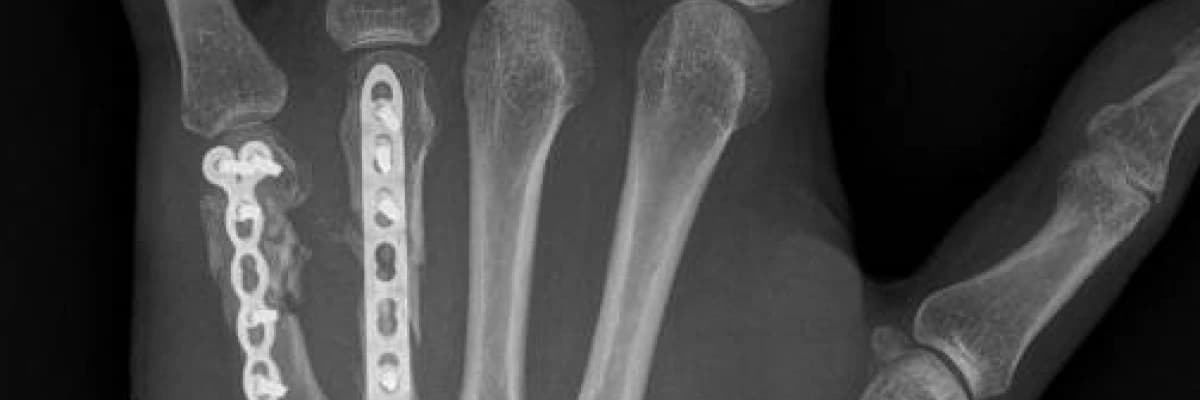

Tedavi planlanırken kırığın radyolojik incelemesi yapılarak şekline, tipine, karakterine ve bulunduğu yere göre en uygun tedavi yöntemi seçilir. Bazı kırıklar alçı yada değişik türde ateller kullanılarak tedavi edilirler. Bazılarına ise ameliyat tedavisi gerekir. Cerrahi tedavide kırıklar düzeltildikten sonra değişik türde metaller ile (çivi, tel, plak ve/veya vidalar) tespit etme ihtiyacı olabilir.